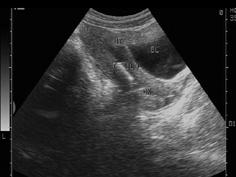

问题 女性,27岁,上环3月,月经量多,超声检查见图,最可能的诊断是 ( )

选项 A、节育器下移 B、节育器嵌顿 C、盆腔炎 D、子宫内膜炎 E、宫颈炎

答案 A